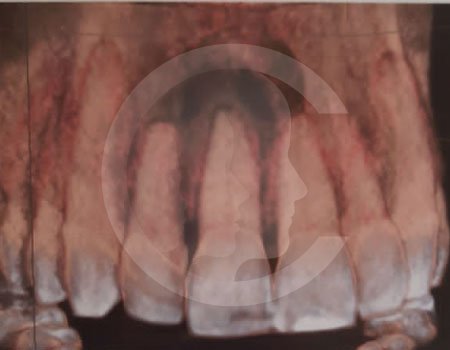

Antes de la extracción se realiza una valoración clínica y estudios de imagen, como radiografías panorámicas o tomografías, para conocer la posición del tercer molar, su relación con los nervios y planificar un procedimiento seguro y adecuado para cada paciente.

No es recomendable. Antes de extraer terceros molares es necesario realizar una valoración clínica y estudios de imagen para conocer la posición del diente, su relación con los nervios y el tipo de procedimiento más seguro para cada paciente.